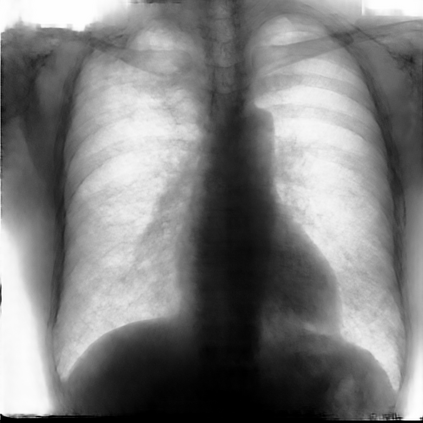

Multi-organ segmentation of X-ray images is of fundamental importance for computer aided diagnosis systems. However, the most advanced semantic segmentation methods rely on deep learning and require a huge amount of labeled images, which are rarely available due to both the high cost of human resources and the time required for labeling. In this paper, we present a novel multi-stage generation algorithm based on Generative Adversarial Networks (GANs) that can produce synthetic images along with their semantic labels and can be used for data augmentation. The main feature of the method is that, unlike other approaches, generation occurs in several stages, which simplifies the procedure and allows it to be used on very small datasets. The method has been evaluated on the segmentation of chest radiographic images, showing promising results. The multistage approach achieves state-of-the-art and, when very few images are used to train the GANs, outperforms the corresponding single-stage approach.